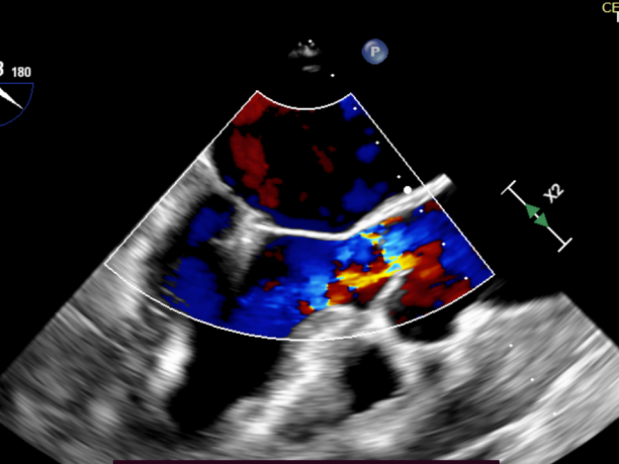

患者全麻后在超声和射线引导下穿刺股静脉-房间隔,器械顺利到达病变的二尖瓣区域,成功完成二尖瓣夹合后,患者二尖瓣反流即刻显著下降,左房压力即刻减低,预示着患者的临床症状将会得到明显改善。